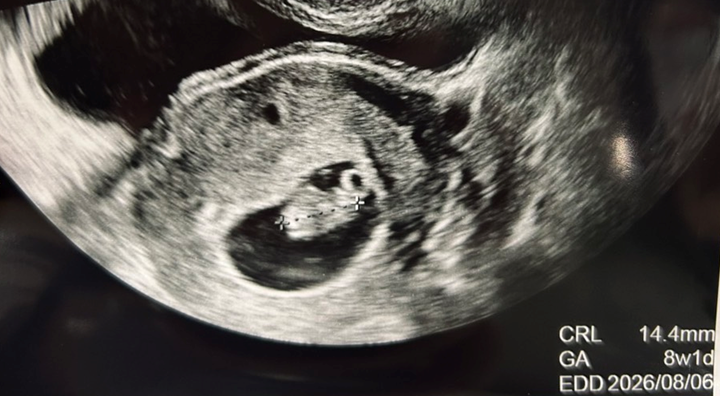

こちらが今回のエコー写真です。

すごく気になったのが、「CRL 14.4mm」の文字。

前回不妊治療クリニック卒業の際に測ったときのCRLは13.2mmでした。

この1週間で1mmしか大きくなっていない。

この時期のCRLの成長スピードは、1日約1mmが理想的。

そんな中、1週間で1mmしか育っていないのは、成長が止まってしまったとしか思えない。

また、先ほど載せたエコー写真には

「CRL 14.4mm GA 8w1d」

という表示が出ていました。

つまり、この産院で使用しているエコー機械の基準では、8週1日相当の問題ないサイズと判断されていた、ということになります。